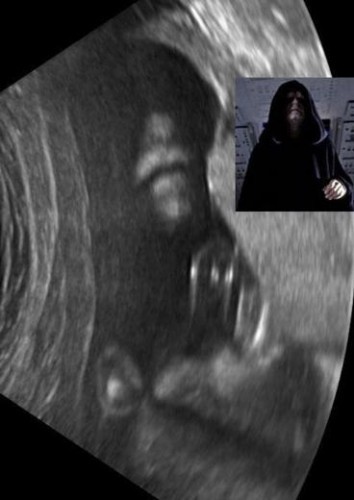

Bebeklerinin bu ilk görüntüsüyle anne-babalar şoke oldu!

Canavar